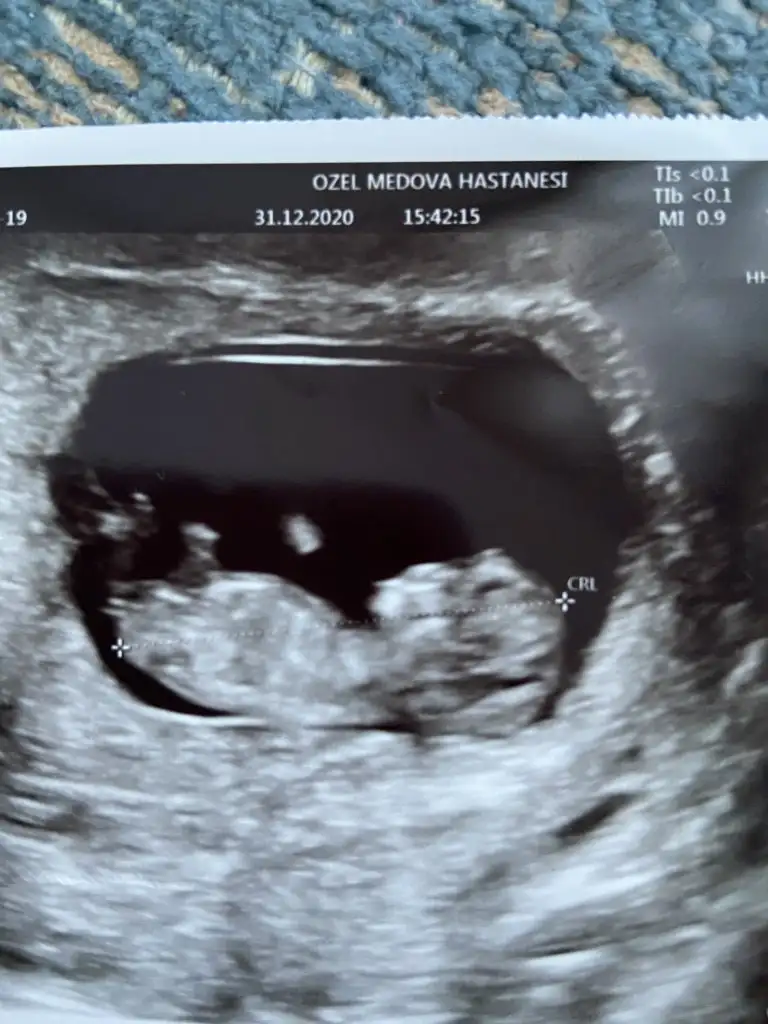

Canım bana parelel gibi görünmüştü kaç gündür anlamaya çalışıyorumErkek görünüyor

Popoya paralel değilCanım bana parelel gibi görünmüştü kaç gündür anlamaya çalışıyorumresim üzerinde tarif edebilir misin nasıl dik göründü sana

Evet kız görünüyorMerhaba benim usg görüntüm videodan o yüzden net olmayabilir tekrar gönderirim isterseniz. 12+0 doktor muhtemelen kız dedi. Şu beyaz görünen nub mı acaba? Bana da tahminde bulunur musunuz?

Erkek görünüyorIkra meyra ve mesajımı okuyan diğer kızlar,rica etsem bir tahminde bulunur musunuz :)